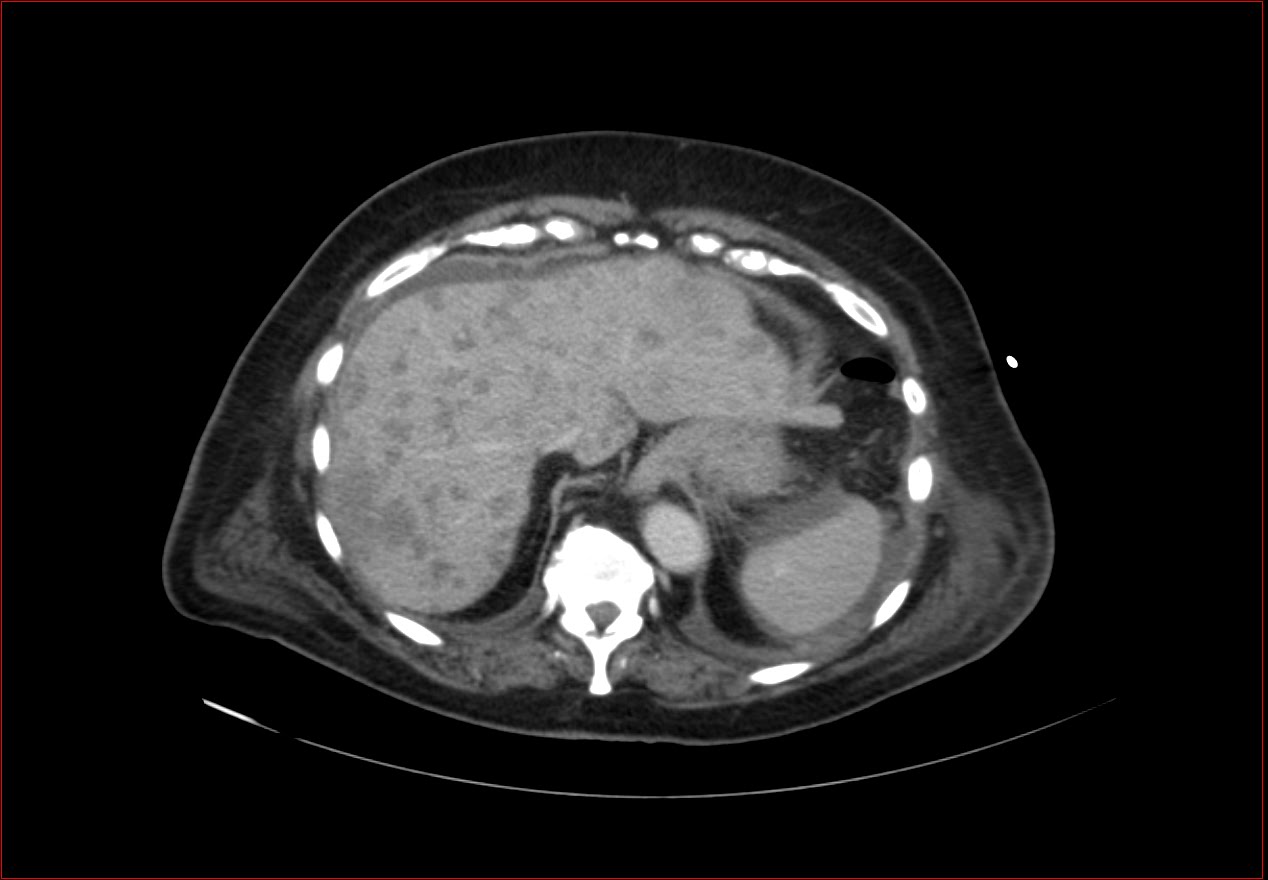

eros hasi fajdalom miatt kertek a 78 eves no vizsglatat, korabban egy keves hasi folyadek jol latszott UH-al, az elozmenyben ezen kivul nagy B-sejtes lyphoma duodenalis erintettseggel (akarmit is jelentsen ez). Mas betegseg nem ismert.

Pneumoperitoneum

az ok nem ismert